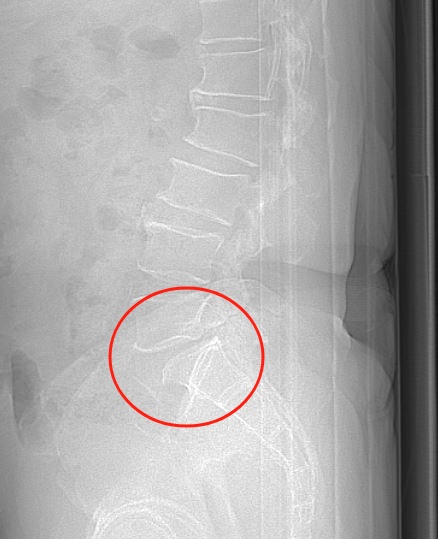

腰椎CT